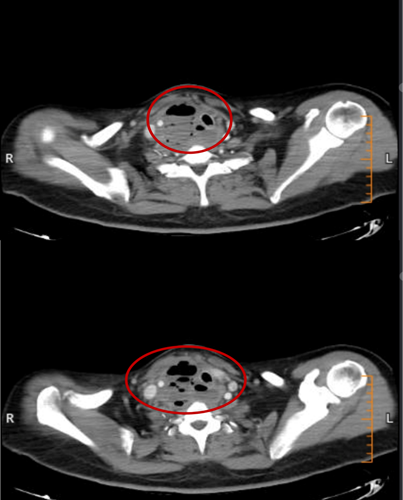

患者乙CT示:颈部咽后间隙—右侧咽旁间隙—右侧颈动脉间隙脓肿

2月15日、2月20日,当长沙沉浸在辞旧迎新的欢声笑语中,两位病情凶险的颈部深部脓肿患者先后被推入耳鼻咽喉头颈外科。他们都有多年糖尿病病史,春节期间饮食不规律、作息紊乱、血糖波动大,让原本隐匿的感染如野火般迅速蔓延。其中一位患者的感染已突破颈部间隙,如藤蔓般向下侵入纵隔区域——那里是心脏、大血管、气管的“交通枢纽”,是人体最脆弱的生命禁区之一。CT影像上,脓肿中密布的气腔像一个个危险的信号,气管严重受压,每一次呼吸都变得艰难。而临床研究数据表明,颈深部脓肿并发下行性纵隔炎,病死率为40%~70%。患者的生命,危在旦夕。